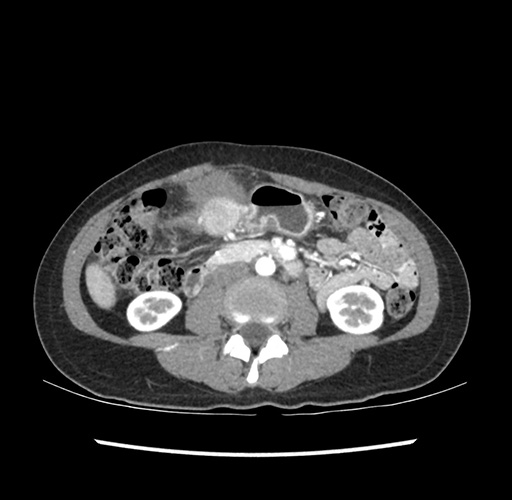

Imaging Analysis

Look through the patient's CT scan to identify any areas of concern for the necessary procedure.

Based on your CT findings, which issue(s) would give reason for "planned slowing down moment(s)" in this case?

Considering a standard left lateral sectionectomy procedure, what step(s) of the operation would you do differently in this case ?